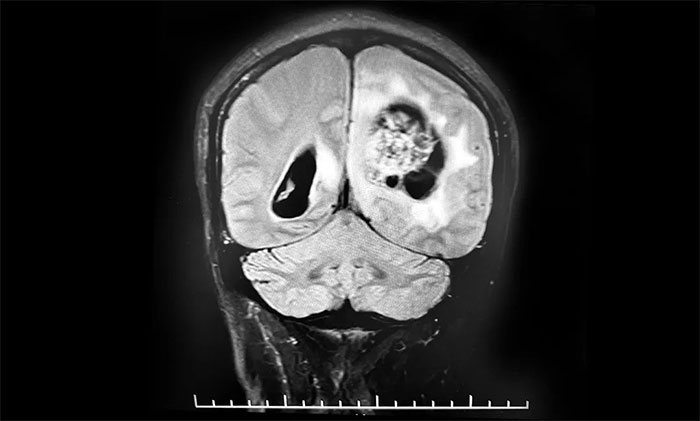

头颅MRI平扫+增强+DWI+MRA提示,左侧顶枕叶巨大肿瘤伴局部瘤卒中,幕上脑室系统、脑干受压变形,中线结构右移19mm,大脑镰下疝形成。李士其教授等专家团队会诊指出,患者脑内巨大占位,性质不明,并且患者已经发生脑疝昏迷,生命危在旦夕,应尽快进行手术治疗,挽救患者生命,同时明确病理诊断。

▲ 左侧顶枕叶巨大肿瘤伴局部瘤卒中